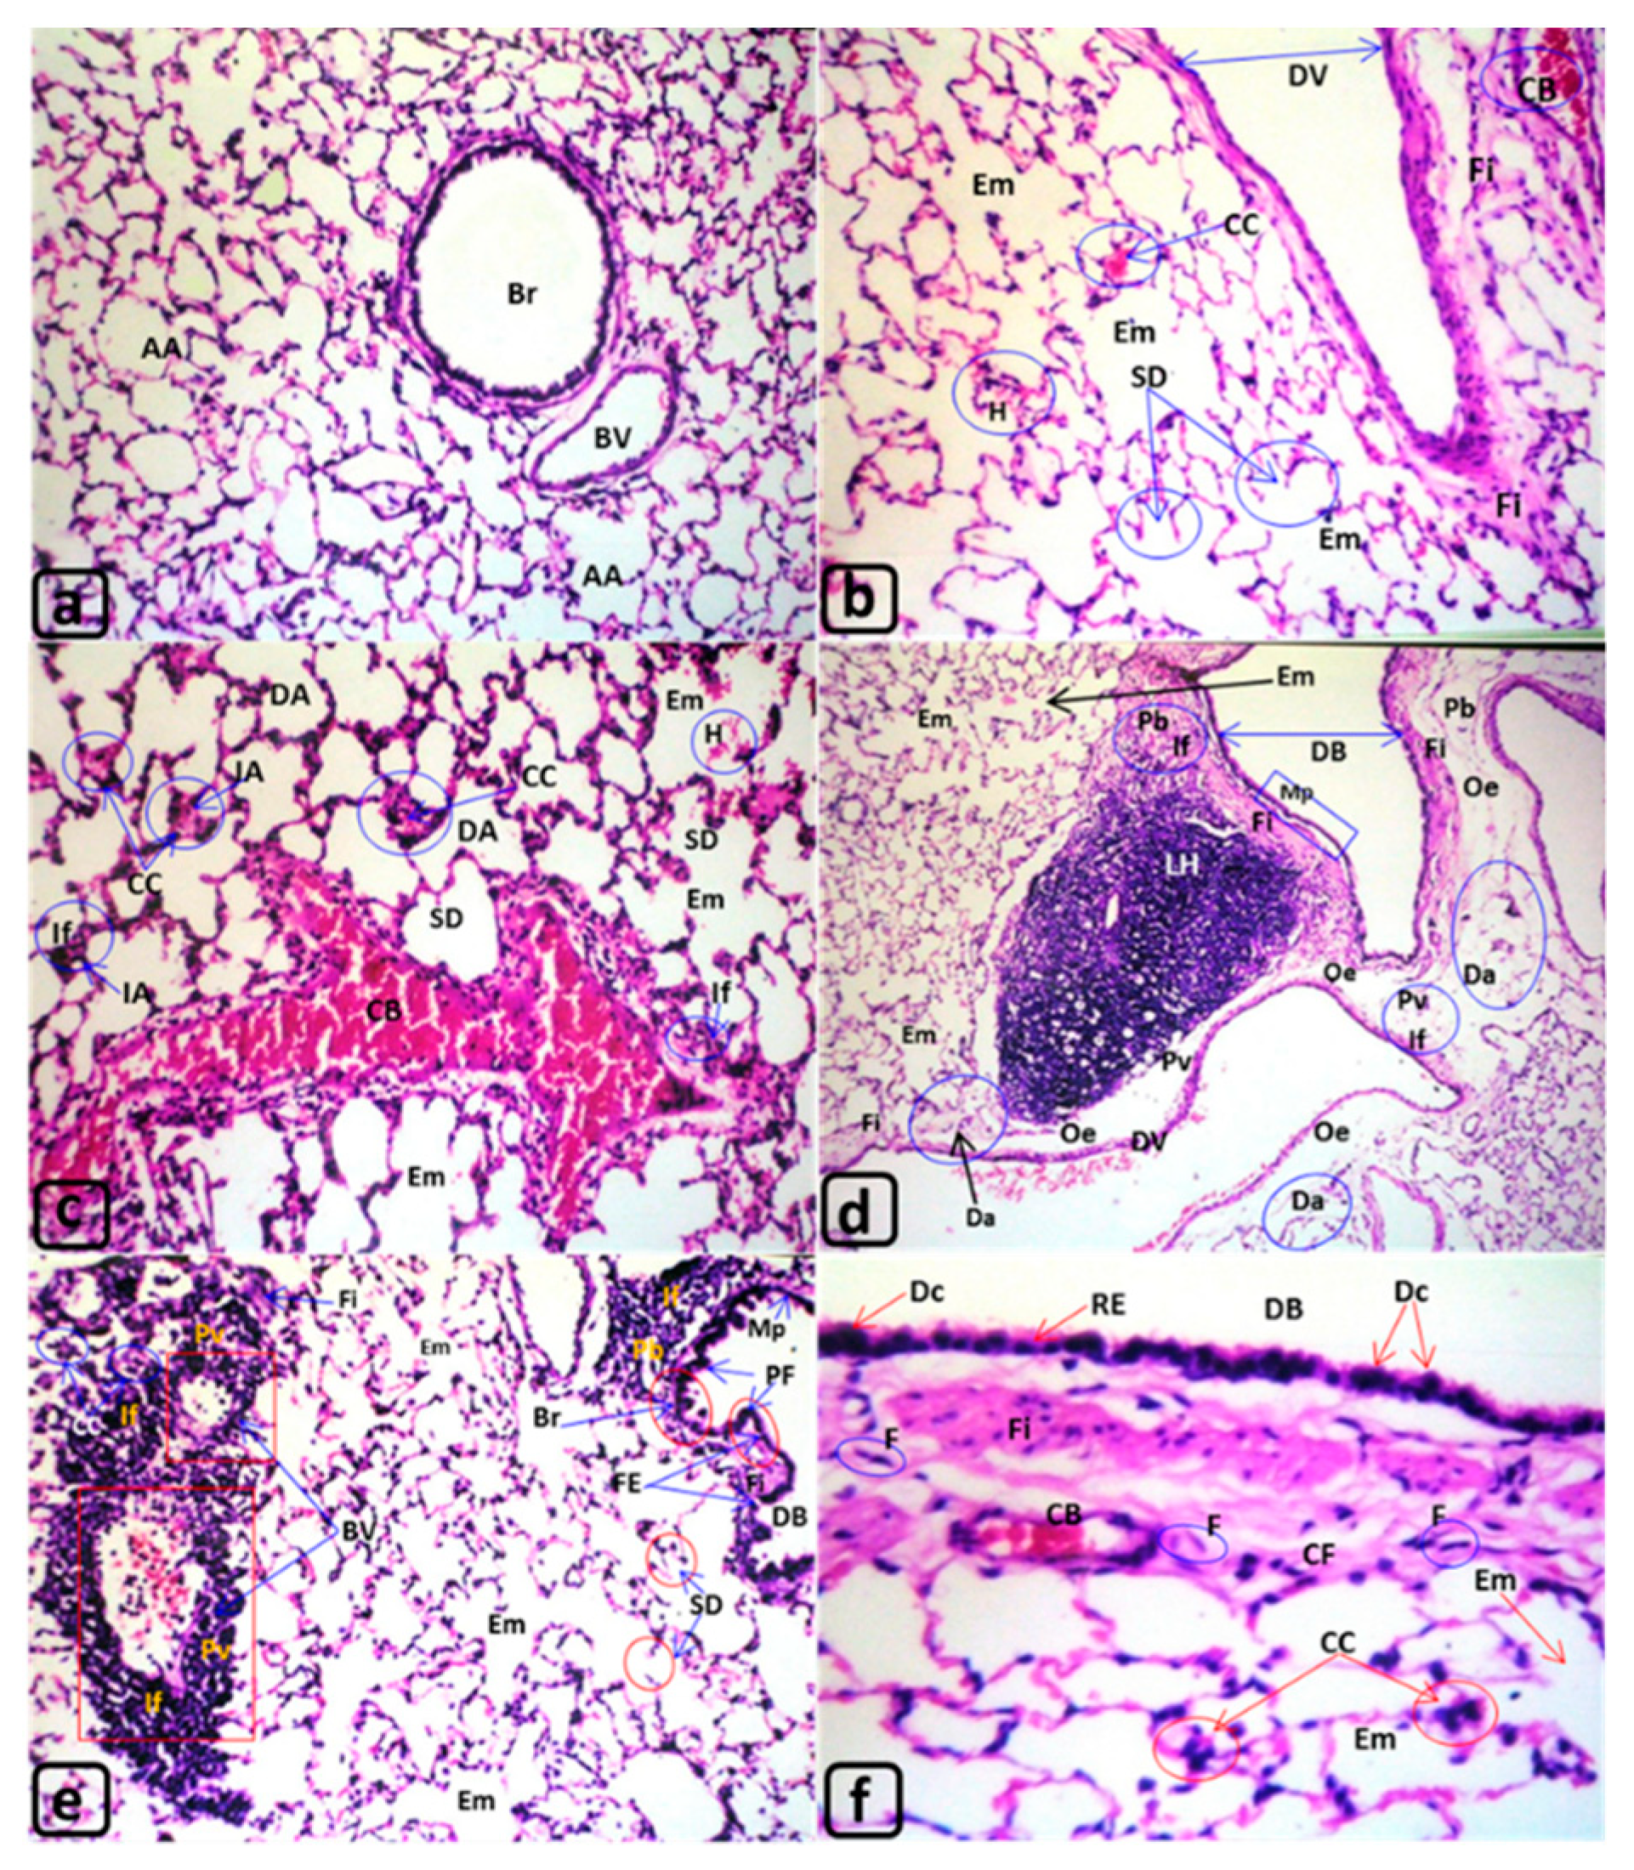

| Lung of Rats Exposed to MTBE Vapor Inhalation 60 µL/3 min/day for 3, 6, or 12 Months | |||||

| Figures | (Figure 1a) | (Figure 3b–d) | (Figure 3e,f) | (Figure 4a–f) | |

| Lumen of Bronchioles “Br” | Normal, Clear | Dilatation in some bronchi “DB” | |||

| Lining epithelia of bronchioles “Br” | Normal | deciliation “Dc” and shortening | --- | ||

| --- | Metaplasia “Mp” | ||||

| --- | Polyp formation PF | Hydroid degeneration “HD” | |||

| Peribronchiolar “Pb” and perivascular “Pv” connective tissue “CT” | Normal | --- | --- | Pulmonary fibrosis Fi | |

| --- | --- | Foam cells “FC” | |||

| --- | --- | Steatosis “St” | |||

| Lymphocytic infiltrations “If” | |||||

| large lymphoid hyperplasia “LH” | |||||

| Edema “Oe” | |||||

| fibroid changes “Fi” | |||||

| Lumen of air alveoli | Normal, Clear | --- | --- | Collapsed alveoli CA | |

| --- | --- | Dilated lumen with Epithelialization Epi | |||

| Hemorrhages “H” | H + Diffuse “DH” | ||||

| Epithelia of air alveoli “AA” | Normal | Emphysematous changes “Em” | Severe Em | ||

| Desquamation “Ds” | |||||

| Shortening with deciliation “Dc” | Degenerated (De) in some air alveoli (Da) | De, Da, metaplasia “Mp”, or thickening “Th” | |||

| --- | --- | Polyp’s formation “PF” | |||

| Interalveolar septa of air alveoli “IA” (Interalveolar CT) and perivascular CT | Normal | Destructed septa “SD” | |||

| Inflammatory cells infiltrations “If” | If with monocytic infiltration “M” | ||||

| Destructed septa “DS”, sever dilated (DV), congested vessels (CB), & capillaries (CC) | Lymphoid hyperplasia “LH” | ||||

| Adenomatous changes (lung adenoma) “LA” | |||||

| Abscess with central liquefaction “CL” covered by pyogenic membrane “PM” | |||||

| Fibroid changes “Fi” | “Fi” with diffused fibrocytes “F” | steatosis (St) with Fi | |||

| --- | --- | Numerous lipid-laden macrophages “Foam cells” “FC” | |||

| ---- | ---- | Mitotic figure “MF” | |||

| Focal hemorrhages “H” | H + Diffuse DH | ||||

| Blood vessels of CT “BV” | Normal | Dilated vessels “DV” | Occluded lumen | ||

| Congested blood vessels “CB “, Dilatated and Congested blood capillaries “CC” | |||||

| Arterial alterations in tunica intima “TI”, tunica media “TM”, and tunica adventitia “Ad”, | Normal TI, TM & Ad | --- | --- | Desquamation “Ds” in TI | |

| --- | --- | Thickening TM & Ad | |||